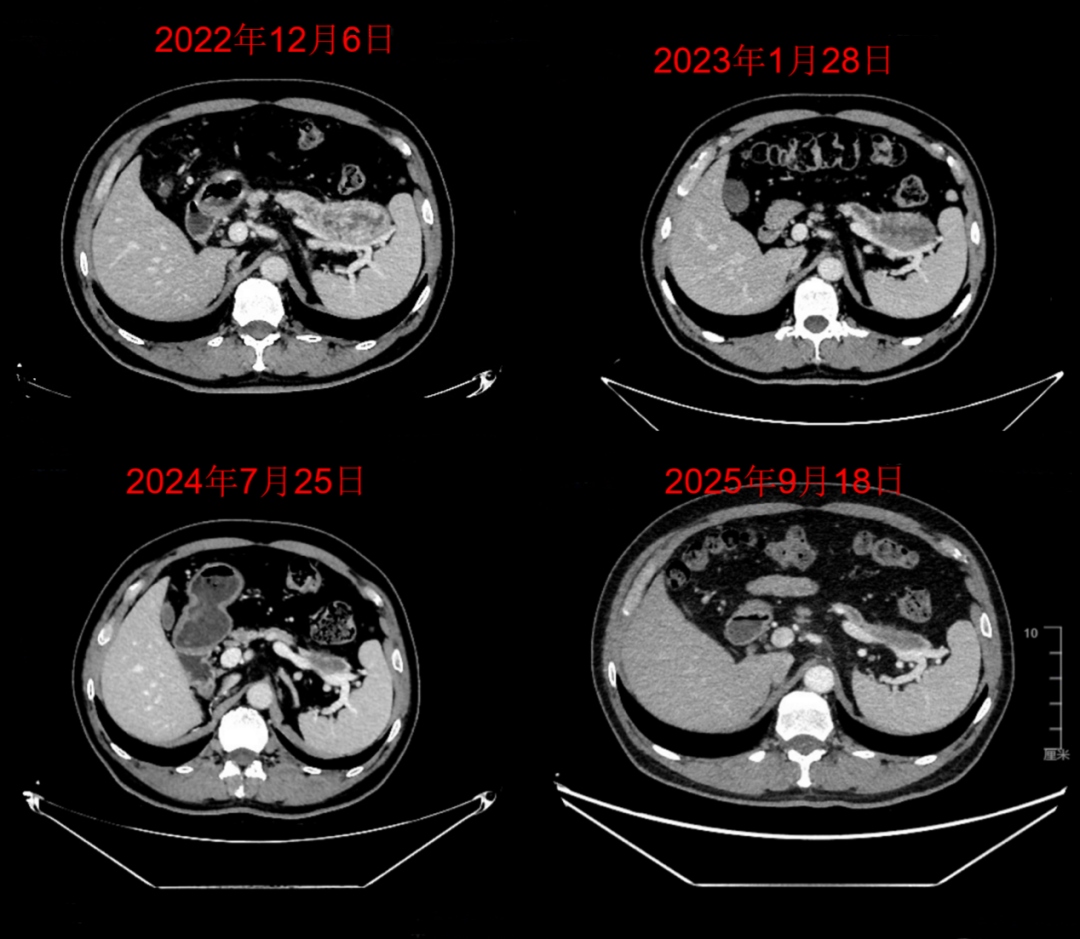

上腹部CT(2022年12月6日,本院):胰尾部、胰颈部及钩突部可见低密度或混杂密度病灶,大小分别约为6.5×4.0cm、3.5×2.5cm和2.0×2.0cm,动脉期和延迟期可见边缘轻度强化,考虑转移癌。

2023年1月:影像学评估为疾病稳定(SD)。

2023年6月:影像学评估为部分缓解(PR)。

2025年9月:影像学评估为部分缓解(PR)。

2026年3月:影像学复查持续维持PR,达39个月。

△基线(2022年12月6日)及不同时间点随访的上腹部CT胰尾部肿瘤变化